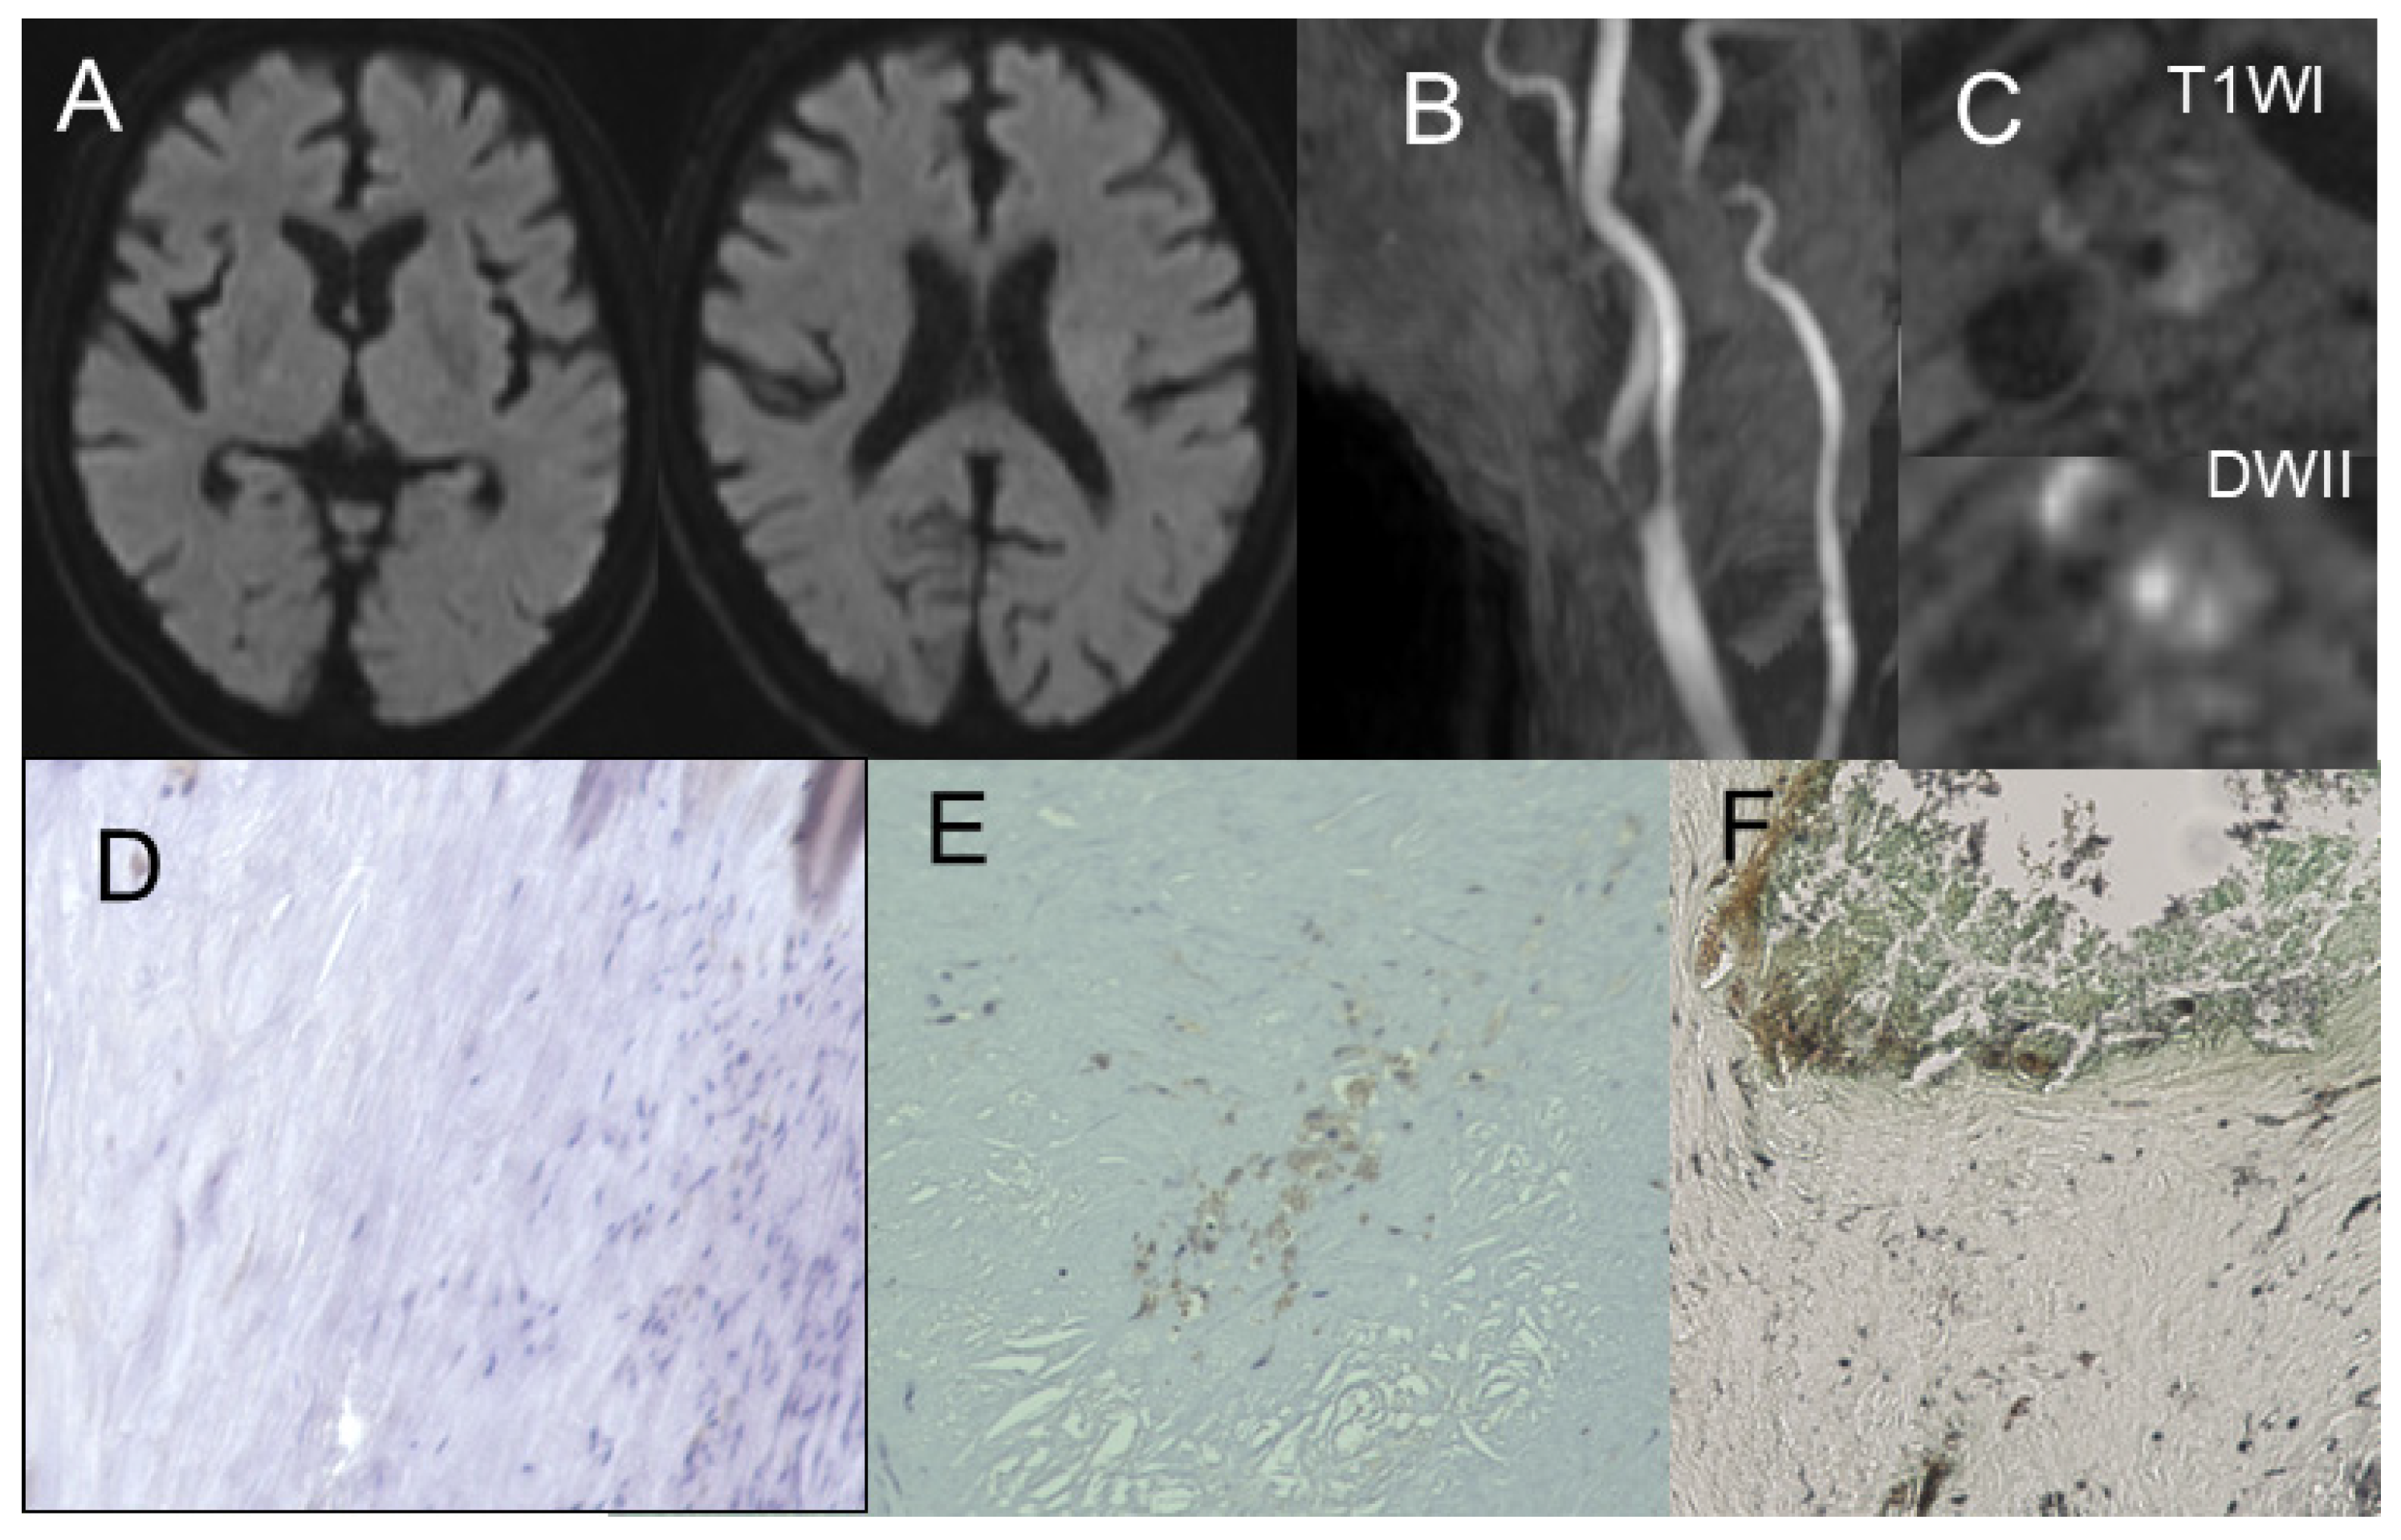

3.2. Gomori’s Methenamine Silver and HE Staining

3.3. Correlation Between Radiological Findings and Plaque Pathology

3.4. MSU Deposits Detected Using DECT and Its Accuracy